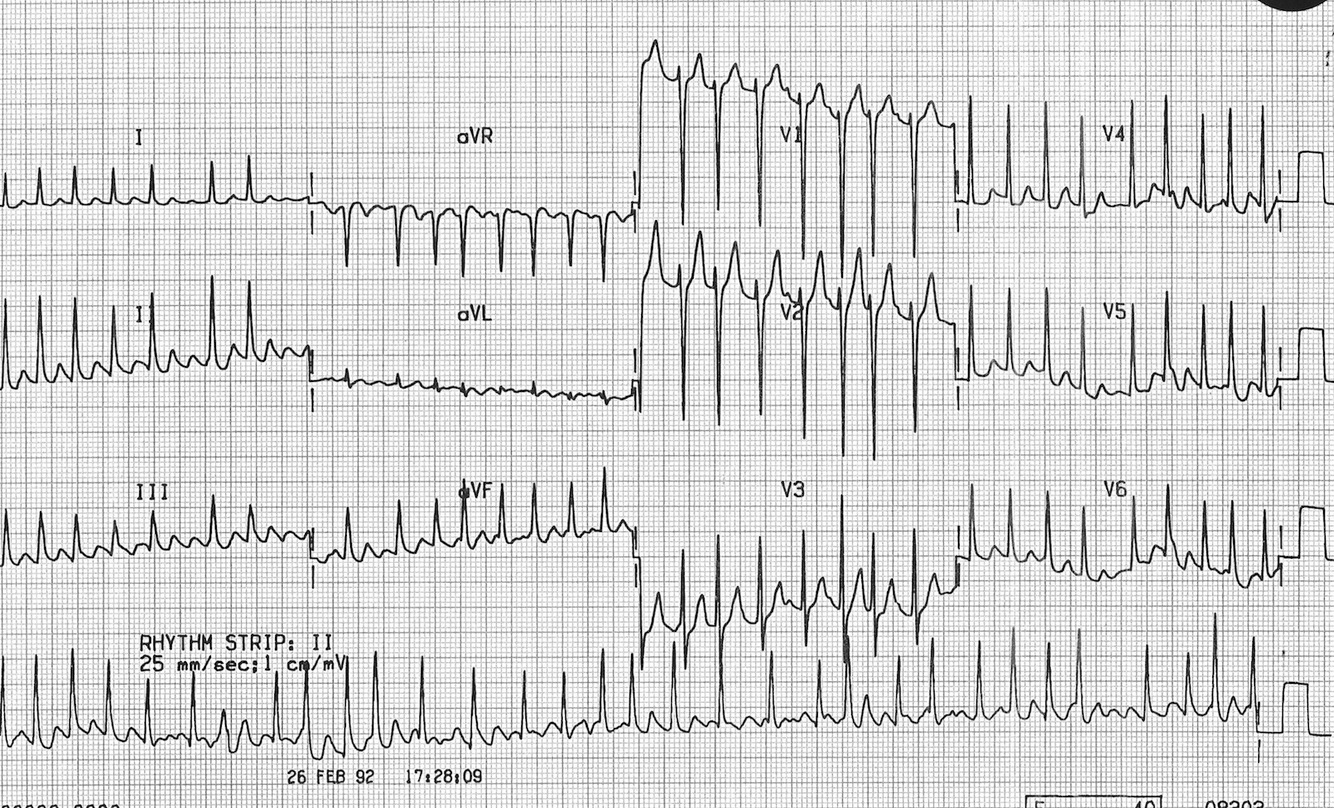

Ventricular Tachycardia (Monophasic)

Broad complex QRS

Regular rate

signs of AV dissociation (may have to look hard for this)

Causes: Cardiomyopathy, IHD, HOCM, Brugada Syndrome.

Urgent transfer to ED